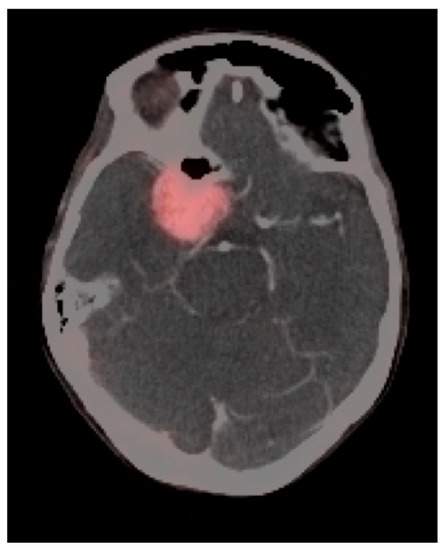

3.5. Brain Metastases

- Galldiks, N.; Langen, K.-J.; Albert, N.L.; Chamberlain, M.; Soffietti, R.; Kim, M.M.; Law, I.; Le Rhun, E.; Chang, S.; Schwarting, J.; et al. PET imaging in patients with brain metastasis-report of the RANO/PET group. Neuro-Oncology 2019, 21, 585–595. [Google Scholar] [CrossRef]